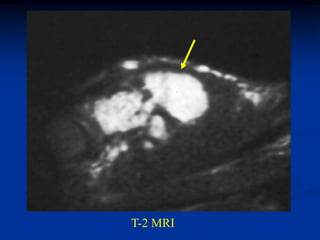

T-2 MRI